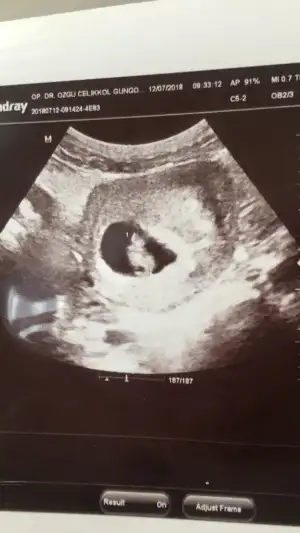

Bu da ilk görüntüsü idi karından:)

Bu 4cu gebeligim daha onceki 3 cu tahmin etmistim 💯 de 💯 tutmustu simdiki belirtilerimde kiz yonunde ama nedense bir surpriz olacakta erkek olacak gibi geliyor bana bayramda orenicez artik sonucu yazarim canim benim ama insallah kizdir 🧿🙏🤭

diğerlerinin cinsiyeti neydi canım 😊 Allah gönlünden geçeni nasip etsin